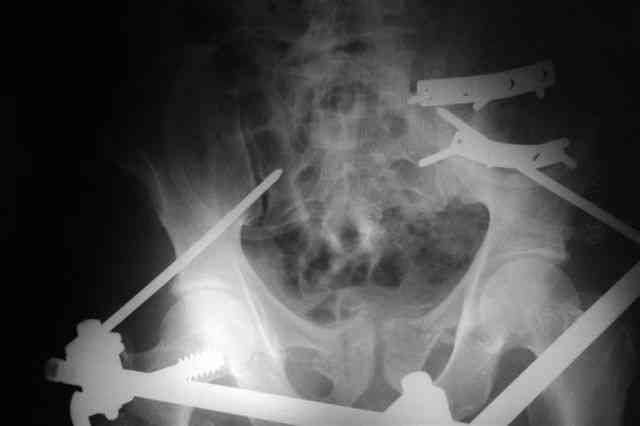

Я помню технику транссакральной фиксации тазового кольца длинными 5 мм Шанцами - повреждения типа В, в этом же случае задний отдел тоже вовлечен

т.е комбинированная нестабильность, поэтому вопрос - достаточно ли только двух Шанцев для стабилизации таза? Что вы думаете об anterior Right SI joint plating + tension band plating from the back.?

PS после фиксации бедра под Эопом посмотрел инлет и аутлет проекции, насколько репонируемо смещение правой половины таза *невооруженными*

руками - никаких шансов улучшить позицию иначе бы конечно воспользовался длинными Шанцами сразу после бедра.

Элегантная фиксация, поздравляю.Но ваш случай : одноплоскостная горизонтальная нестабильность Tyle B2.2 отличен от представленного мной - у

моего больного + вертикальная нестабильность за счет повреждения правого крестцово-подвздошного сочленения и перелома заднего отдела подвздошной

кости- С2 тип. Поэтому и возникла дилемма : выбор оптимальной фиксации заднего отдела:

По-поводу фиксации таза спонгиозными винтами. Данный способ все-таки показан для фиксации повреждения крестцово-подвздошного сочленения или переломов крестца. Мне кажется, что в данной случае ситуация иная - имеется перелом "основания" крыла подвздошной кости (в который вовлечена и поверхность, составляющая крестцово-подвздошное сочленение). Не уверен, что фиксация данного повреждения (и заднего полукольца) винтами будет стабильной, так как именно на уровне 1-2 крестцовых позвонков (где обычно вводят винты) линия перелома уходит в латеральном направлении от крестцово-подвздошного сочленения.

Я просмотрел томограммы и у меня создалось впечатление, что винтам есть за что *зацепиться*. В сочетании с 5 мм Шанц винтами, проведенными через нижне-переднюю ость спереди назад через КП сочленения -стабильность тазового кольца должна восстановиться. - Это , конечно, при условии , что закрытая рнепозиция будет успешной.

после КТ отказался от этой идеи - двусторонний перелом крестца в зоне 1 - алярная часть, при попытке низведения правого гемипелвиса теоретически есть вероятность смещения

фрагмента крестца слева.